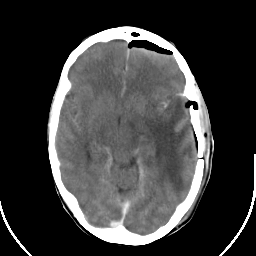

Metastatic bronchogenic carcinoma: Roentgen-ray CT (post-op) -- Slice #9

[Home][Help][Clinical] Slice 9